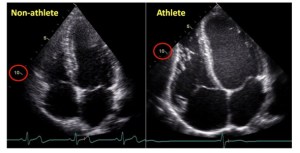

– Heart volume and size increases (Left Ventricle)